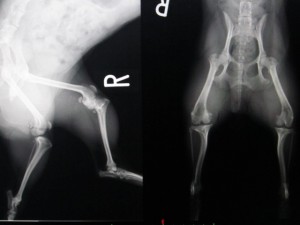

術前のレントゲンです。

両側膝蓋骨脱臼も見られます。